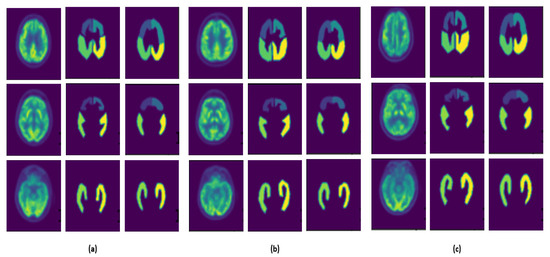

- U-Net3D, which is the original architecture composed of three encoder and decoder layers (Figure 2a);

- U-Net3D-NoMaxPoolingThirdDimension, where, for each layer, MaxPooling is not applied to the third dimension (Figure 2b). The network acquires more information for each layer, and a higher number of parameters must be estimated during the training phase;

- U-Net3D-TwoLevel (Figure 2c), which is a model characterized by eliminating one layer from the original architecture, reducing the number of parameters.